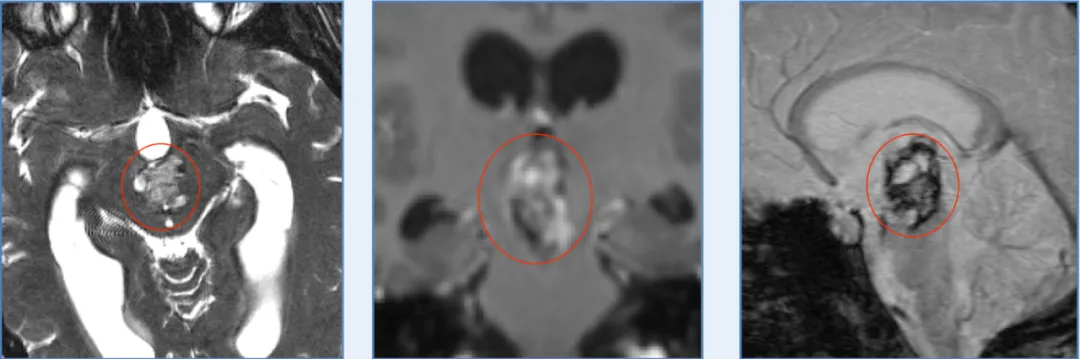

头痛、恶心与呕吐——21岁的Lily不曾预料,这些看似平常的身体信号,竟是脑干出血的临床表现。作为一名在校大学生,她原本对未...